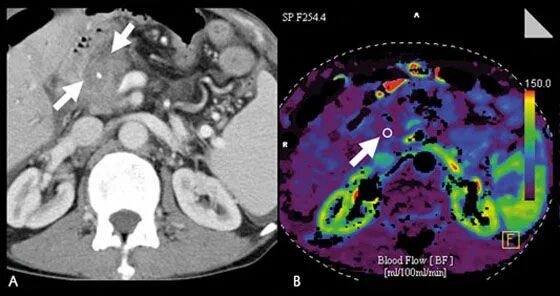

Плохо после контраста кт